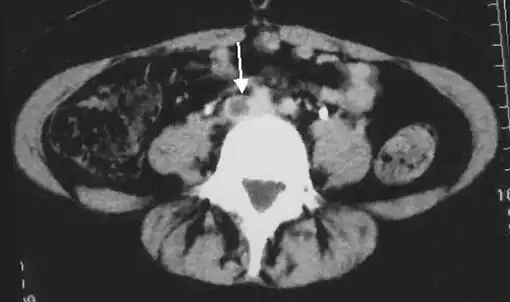

- An abdominal CT scan demonstrating an iliofemoral DVT, with the clot in the right common iliac vein of the pelvis